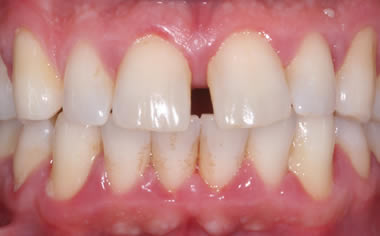

Case Two (2 images)

Treatment of moderate gum disease.